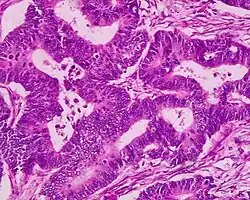

Als Adenokarzinom bezeichnet man einen bösartigen (malignen) von der Deckzellschicht (Epithel) ausgehenden Tumor, der aus Drüsengewebe hervorgegangen ist. Die gutartige (benigne) Zellveränderung von Drüsengewebe nennt man dagegen Adenom.

Adenokarzinome lassen sich im Rahmen der pathologischen Aufarbeitung aufgrund ihrer Gestalt (Morphologie), ggf. Schleimsekretion (Muzingehalt) und Proteinausstattung typisieren sowie teilweise auch dem Ursprungsorgan zuordnen, was insbesondere bei Metastasen wichtig ist, um den Ausgangstumor (Primärtumor) aufzuspüren (vgl. CUP-Syndrom). Zusammengefasst:

- Morphologisch besser differenzierte Adenokarzinome zeigen ein „drüsiges“ Wachstum, z. B. in Röhren (tubulär, azinär, duktal) oder siebförmig (kribriform). Andere Wuchsformen sind z. B. papillär (fingerförmig) und mikropapillär (knospenartig).

- Schlechter differenzierte Adenokarzinome wachsen oft „am Stück“ (solide) oder einzelzellig (diffus) und können ggf. nur mittels Zusatzuntersuchungen von anderen Karzinomen wie z. B. einem schlecht differenzierten Plattenepithelkarzinom unterschieden werden. Mischform: adenosquamöses Karzinom.

- Schleimbildung: Extra- oder intrazelluläre Schleimansammlung, am HE-Schnitt oder mittels PAS-Diastase-Färbung darstellbar. Extremfälle sind das muzinöse Adenokarzinom (Tumorzellen schwimmen in Schleimseen) und das Siegelringzellkarzinom (die Tumorzellen sind prall mit Muzin gefüllt).